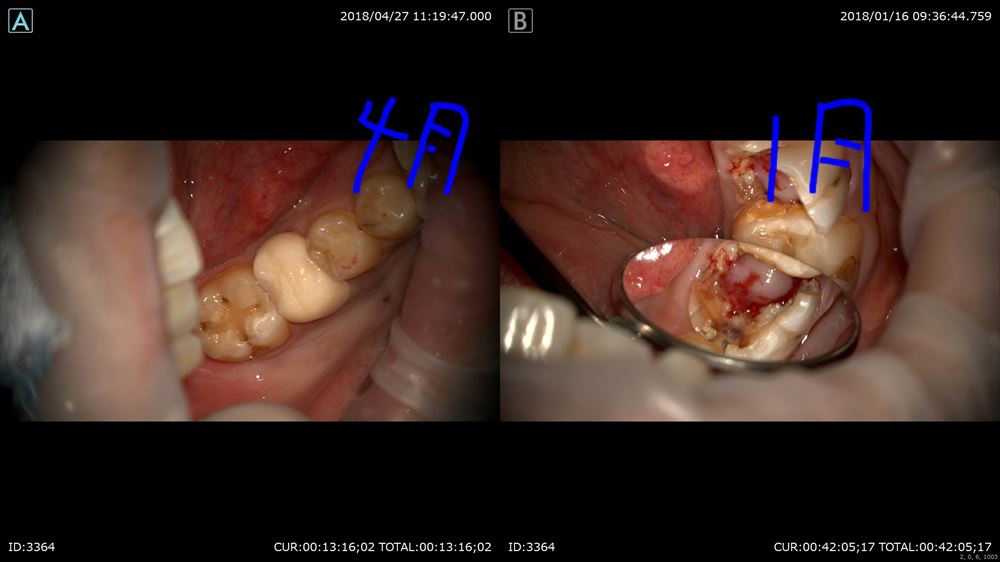

右1月。左4月(まだ仮歯ですが)

歯を抜かずに残せます!!